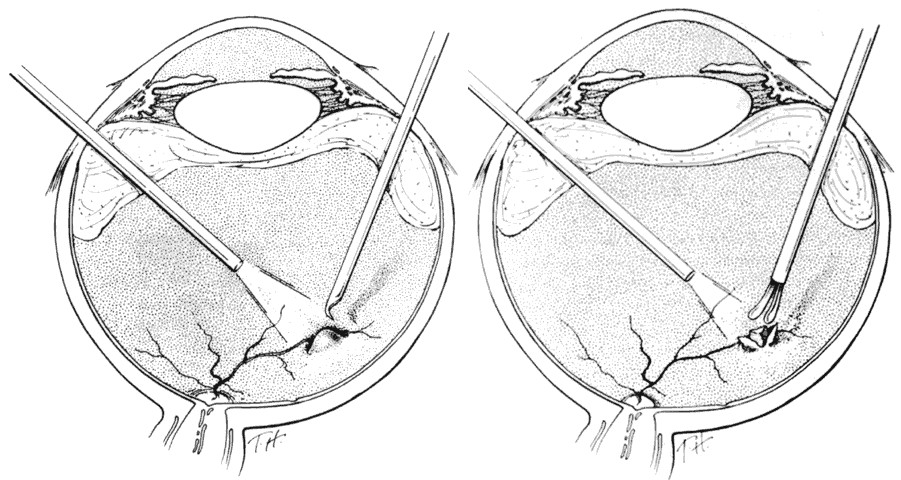

Intraretinal nonmagnetic foreign bodies and embedded magnetic IOFBs unsuitable for posterior transscleral magnet extraction because of their large size, posterior location, or the presence of opaque media are removed by vitreous microsurgery. Intraretinal magnetic IOFBs are not removed by magnet through the pars plana because their passage through intervening retina can produce large lacerations and detachments (Fig. 11).20 Approached and exposed in the same manner described above, they are gently dislodged, grasped with foreign-body forceps, and removed. A lighted pick can be used to manipulate the IOFB into a position or orientation favorable for a secure grip by diamond-coated forceps. Alternatively, magnetic intraretinal foreign bodies may be elevated to the midvitreous by a rare earth magnet, after which they are removed by forceps (Fig. 12) to avoid being dislodged in the vitreous base, as often occurs when extraction by the magnet itself is attempted. Intraretinal foreign bodies of 1 to 2 weeks' duration may become encapsulated (Fig. 13A), in which case the capsule is incised by a myringotomy knife or sharp needle before it can be grasped by forceps or dislodged by the rare earth magnet (see Fig. 13B).

Fig. 13. Removal of encapsulated intraocular foreign body. A. Capsule surrounding foreign body is opened with sharp blade or pick after removal of vitreous gel. B. Exposed foreign body is grasped by forceps and removed. (Michels RG, Wilkinson CP, Rice TA: Vitreous Surgery. Retinal Detachment, p 837. St. Louis, CV Mosby, 1990)A

The vitreous cortex posterior to the equator is removed, if possible, from eyes with intraretinal foreign bodies. If not detached spontaneously, it is separated with a retinal pick (Fig. 14) or by suction with a soft-tipped cannula. The retinal laceration at the site of foreign-body incarceration is surrounded by laser and supported by a localized scleral buckle when the surrounding cortical vitreous cannot be removed. If present, subretinal fluid surrounding the incarceration site is drained internally through the retinal laceration while a fluid-air exchange is performed. Endolaser is applied around the break and the air is replaced by a short-acting gas tamponade.